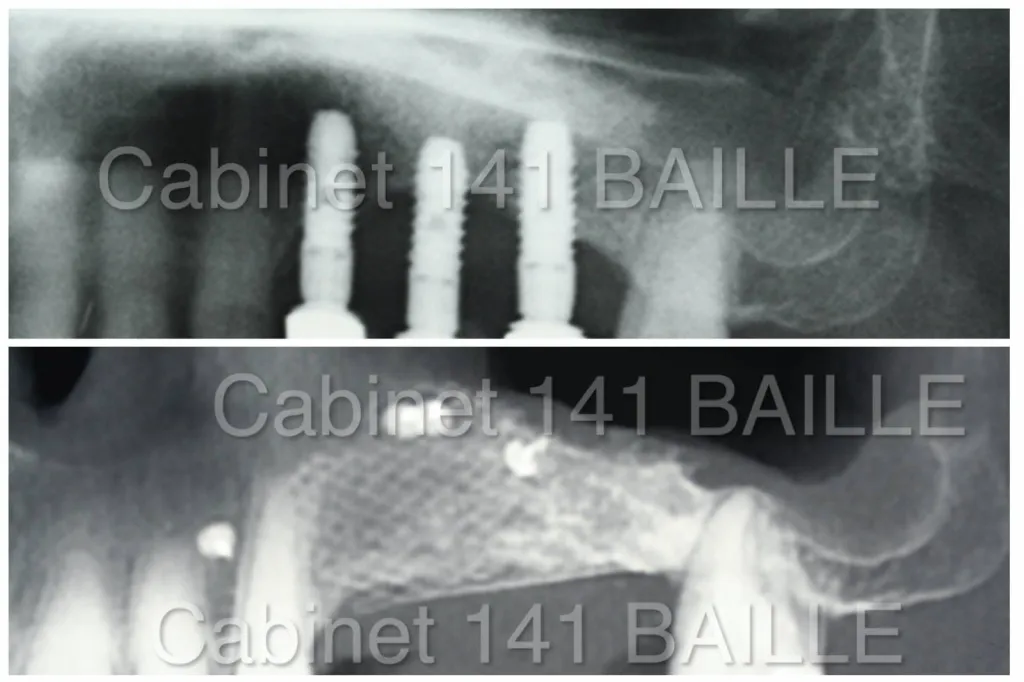

Contrôle implants All-on-6 par spécialiste implantologue à Marseille

Échec All-on-6 : causes, prévention et solutions à Marseille

Échec All-on-6 : comprendre les causes et les solutions expliquées par un spécialiste All-on-6 à Marseille